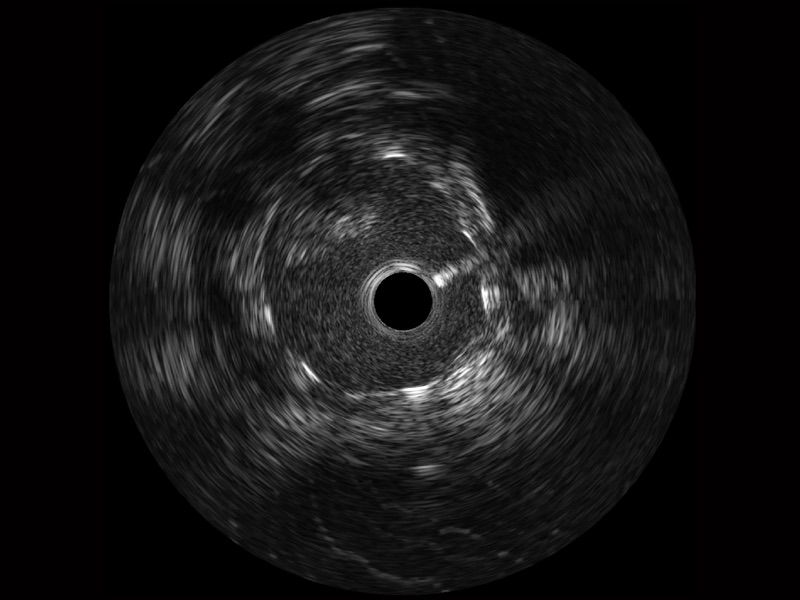

传统IVUS图像

对比传统IVUS导管成像,美狮贵宾会官网宽频IVUS图像的近场支架梁显影更细腻,远场中膜外血管仍清晰可辨,兼顾远中近,兼顾分辨力与穿透深度